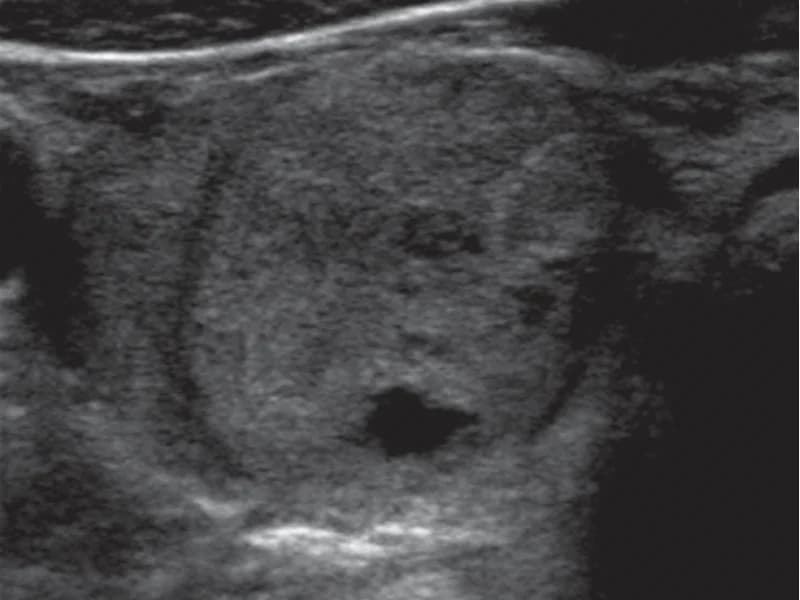

É possível ter Hashimoto com anticorpos negativos?

Sim. 5-10% dos casos de Hashimoto têm anticorpos negativos (Hashimoto seronegativo). O diagnóstico é feito por ultrassom e quadro clínico.